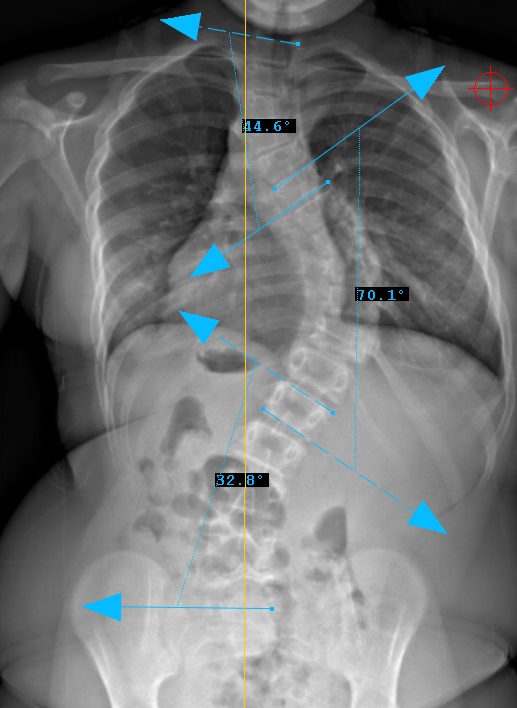

Curve Type 2

proximal thoracic curve structural, main thoracic curve major, lumbar curves non-structural

Lumbar modifier A

CSVL between pedicles at apex (L5)

Therefore, Classification is Type 2A-

Lenke Type II describes a double thoracic curve pattern. The main thoracic curve is considered the major curve as the greatest coronal plane deformity is present between T2 and the T11-12 disc. In Lenke Type II curves, the proximal thoracic spine is also considered structural. By definition, the proximal thoracic spine is structural if the deformity is greater than 25 degrees on side-bending radiographs or if the T2-T5 kyphosis is greater than 20 degrees in the sagittal plane. All lumbar and sagittal modifiers remain applicable in Lenke Type II curves. Often both the proximal thoracic and main thoracic curves are treated with instrumentation and fusion. The UIV is usually T2 or T3 based on shoulder position (high left shoulder fuse to T2) and the LIV is often the stable vertebra (best bisected by the CSVL) in the thoracolumbar junction.

Preop PA View